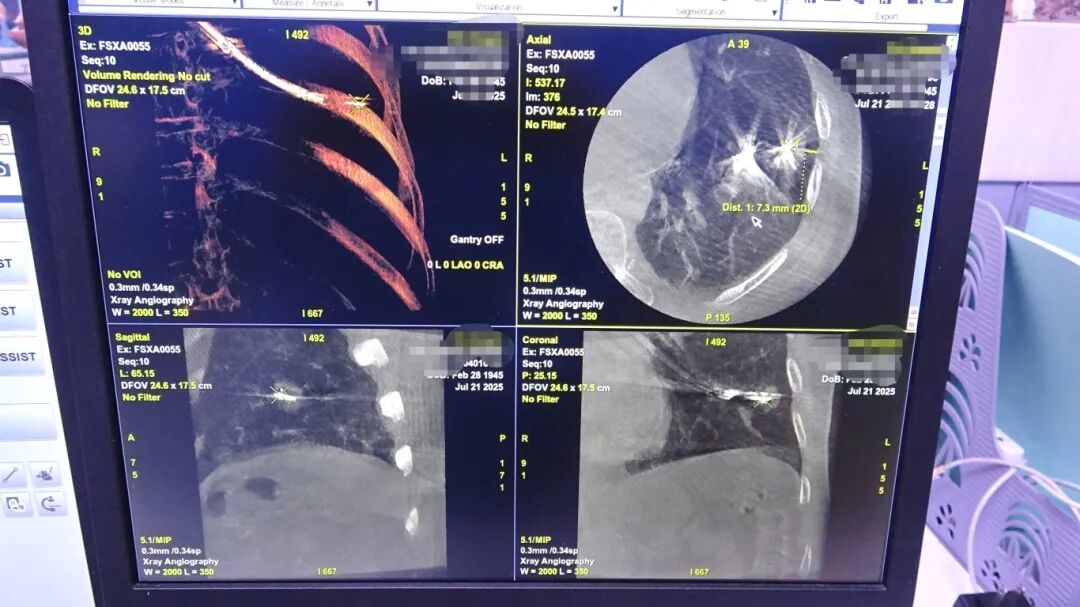

为了进一步提高手术的安全性,李一诗带领气道介入手术团队进行了周密的术前规划。他们打算利用先进的虚拟导航系统,为医生装上了“超级GPS”,规划出抵达病灶的最优路径;使用全球首发的国产呼吸内镜再结合径向超声和锥形束CT(CBCT)这“两双慧眼”,在操作过程中进行多模态实时定位,确保能准确找到那个仅以厘米计、隐藏在肺叶深处的微小肿瘤,实现“指哪打哪”的精准打击。

术中使用设备及射频消融影像